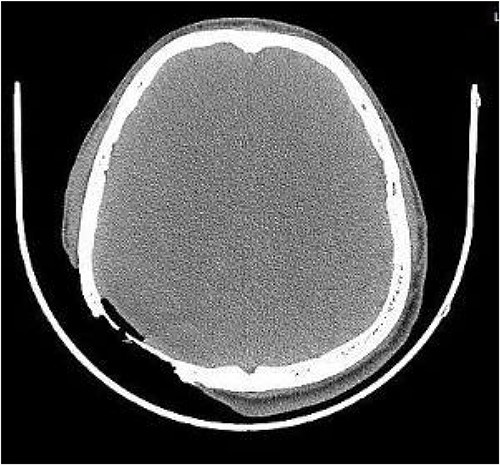

On post-debridement Day 16, the exposed skull was ~8 cm × 9 cm, the bone was dark, and the cortex of the skull defect was ~3 cm × 3 cm (Fig. 1). Computed tomography showed the presence of gas inside the skull (Fig. 2). Bacterial culture of wound secretions reported Proteus mirabilis. During residual wound debridement, a defect of ~1 cm × 1 cm of the inner plate of the skull and dura mater exposure were found (Fig. 3). Subsequently, two skin dilators were embedded under normal scalp and were dilated by regularly injecting saline (Fig. 4). The exposed dura was regularly rinsed with saline to reduce bacterial colonization.